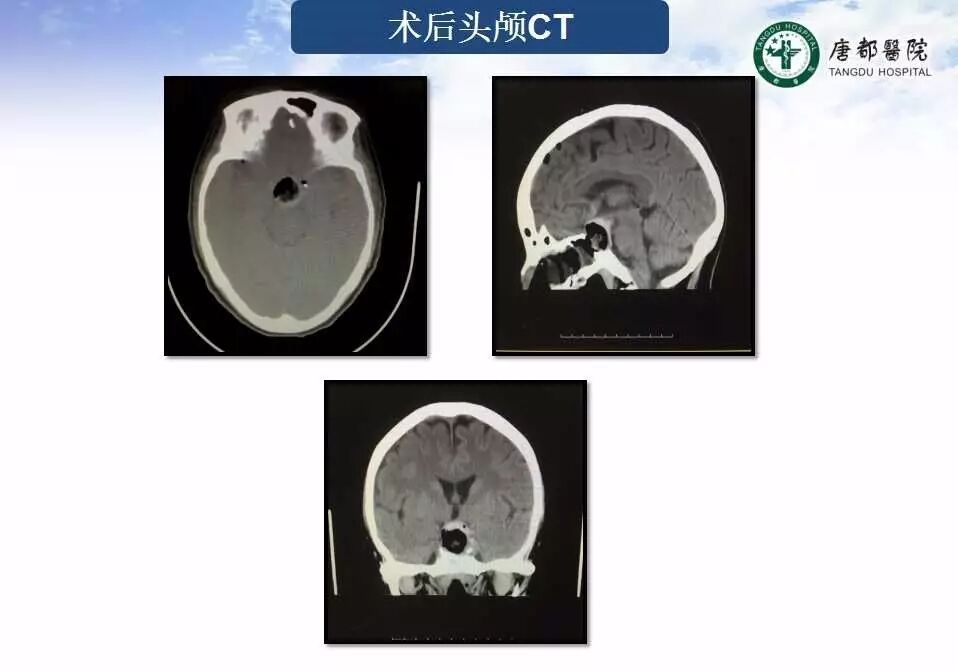

Case 1

长按并识别二维码即可查看该手术视频